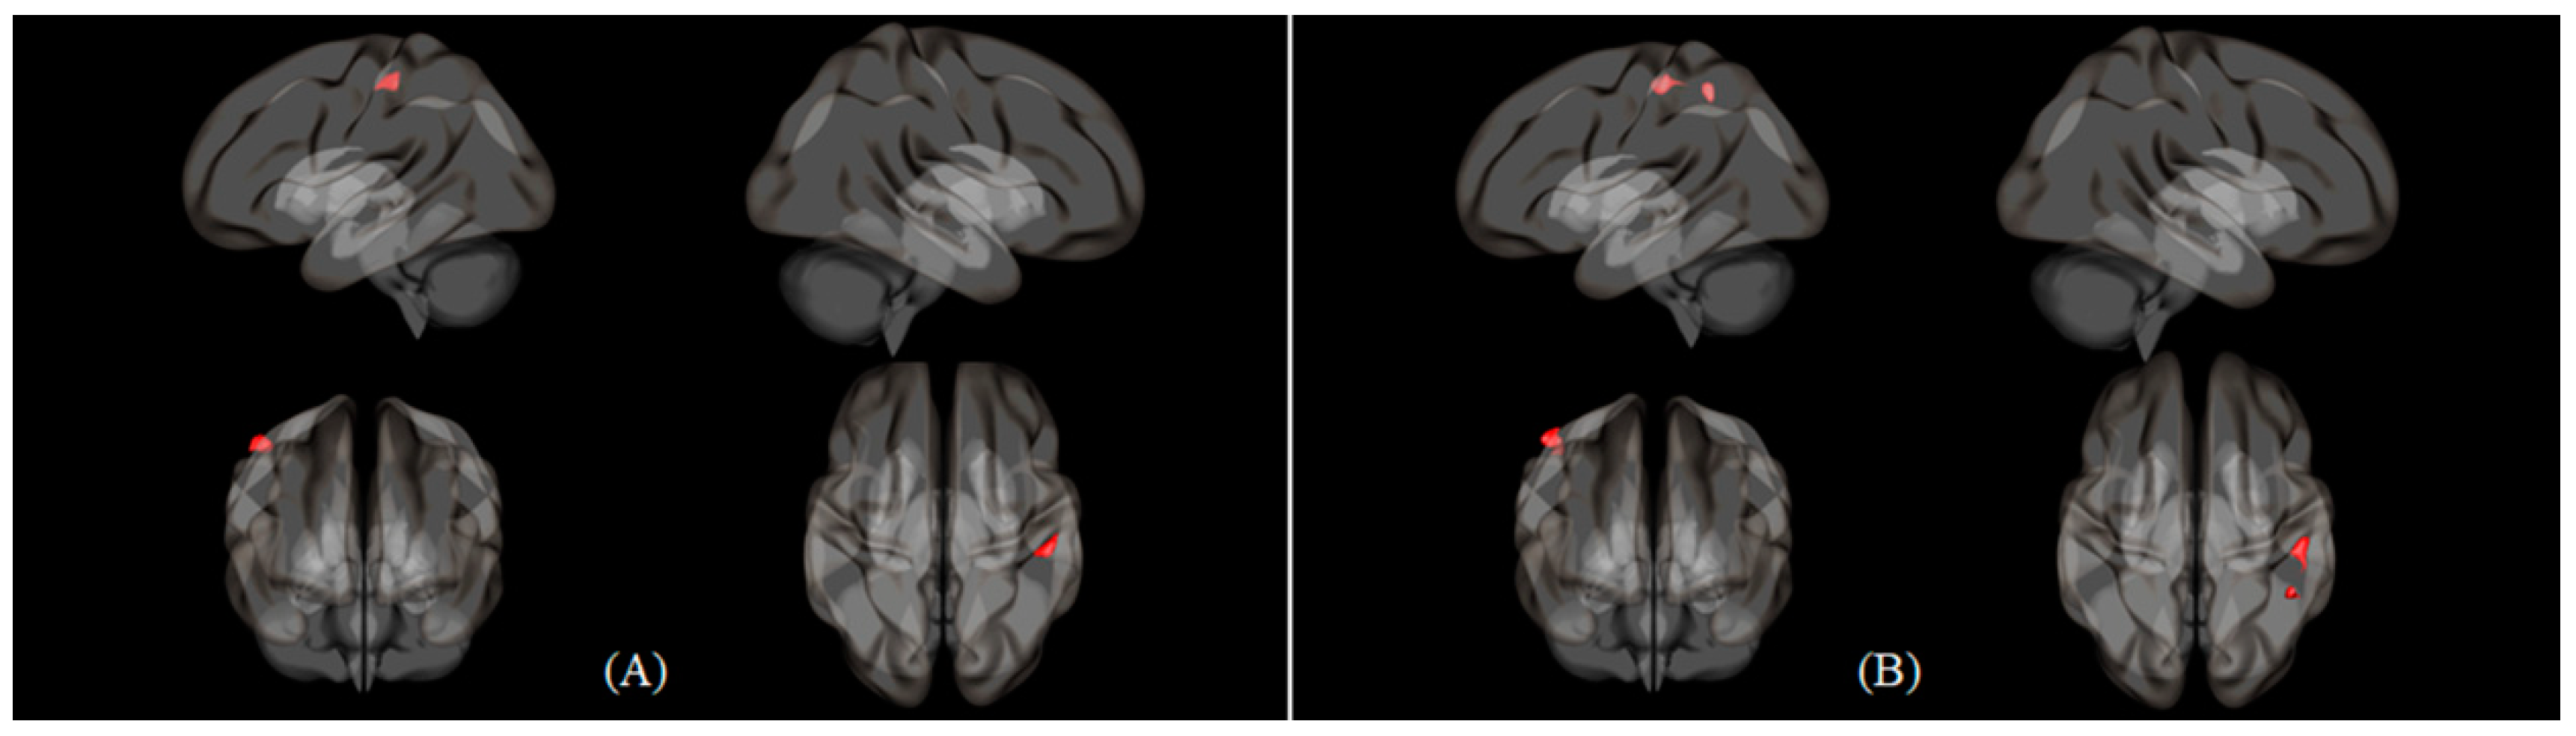

| Condition | Seed | Region | Cluster (KE) | Peak | Peak | Peak MNI Coordinate | ||

|---|---|---|---|---|---|---|---|---|

| T | Z Score | X | Y | Z | ||||

| Nasal > Oral | Cerebellum 6 (L) | Cerebellum 8 (R) | 240 | 5.538 | 4.771 | 36 | −58 | −44 |

| Inferior parietal gyrus (R) | Parietal operculum cortex (R) | 179 | 4.944 | 4.364 | 52 | −34 | 26 | |

| Postcentral gyrus (L) | 114 | 4.617 | 4.129 | −36 | −26 | 48 | ||

| Cerebellum 6 (R) | 115 | 4.241 | 3.847 | 24 | −54 | −24 | ||

| Inferior parietal gyrus (L) | Postcentral gyrus (L) | 239 | 4.927 | 4.352 | −34 | −28 | 48 | |

| Middle frontal gyrus (L) | Anterior cingulate gyrus | 146 | 4.571 | 4.095 | −2 | 14 | 32 | |

| Lateral occipital cortex, (superior division) (L) | 202 | 4.312 | 3.901 | −20 | −88 | 38 | ||

| Oral > Nasal | Inferior frontal gyrus, triangular part (L) | Postcentral gyrus (R) | 123 | 4.620 | 4.131 | 50 | −32 | 56 |

| Middle frontal gyrus (L) | Postcentral gyrus (R) | 215 | 4.449 | 4.004 | 50 | −30 | 54 | |